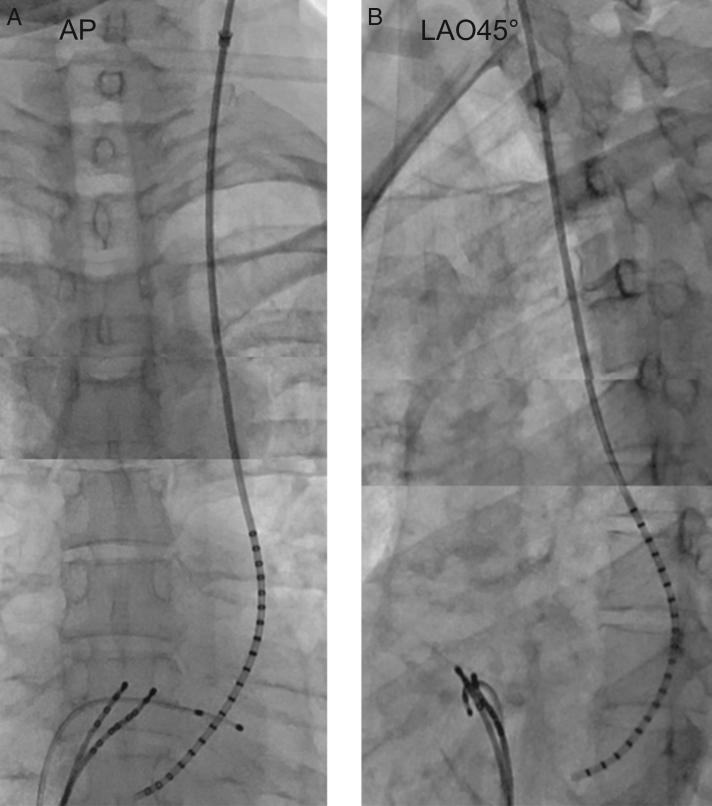

A simple method to ablate left-sided accessory pathways in a patient with coronary sinus ostial atresia and persistent left superior vena cava: A case report.